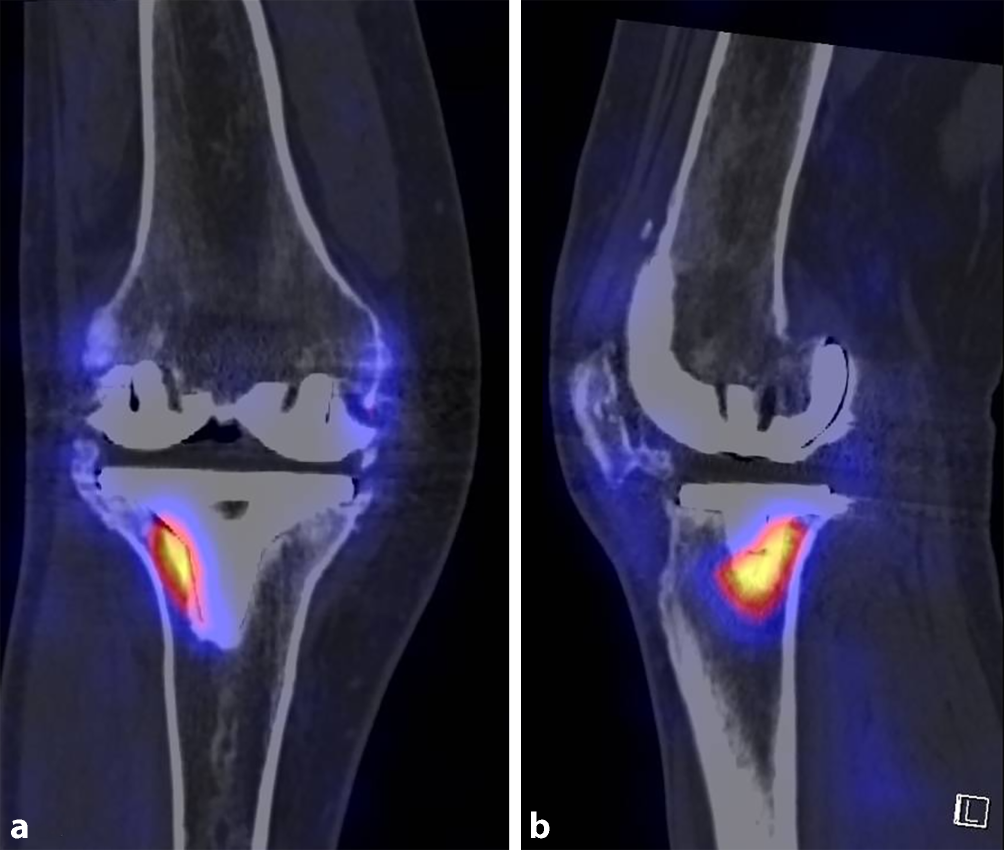

Die kombinierte SPECT- und CT-Bildgebung (Abb. 5; z. B. 99mTc-HDP-SPECT/CT) ermöglicht eine detaillierte Darstellung der Tracer-Aufnahme in Relation zur Gelenkarchitektur, bei guter Reproduzierbarkeit und ist besonders nützlich, wenn konventionelle Bildgebungsverfahren unzureichende Informationen liefern [47, 5052]. Zudem kann die Komponentenpositionierung mit spezifischen Schmerzcharakteristika in Korrelation gebracht werden [36, 51]. In einer Arbeit von Hirschmann et al. konnte eine erhöhte Tracer-Aktivität bei Lockerung, Rotationsfehlstellung oder verändertem Slope mit tibialem, femoralem oder patellärem Tracer-Uptake korreliert werden [35, 47, 53]. Besonders bei Patella baja (Abb. 6) und patellofemoraler Arthrose ist eine erhöhte patellofemorale Tracer-Aufnahme zu beobachten [47, 53, 54]. Entscheidend ist es hier, die Uptake-Muster-Pathologien zuordnen zu können.

Abb. 5

Heterotope Ossifikation, Knie rechts. SPECT/CT in koronarer (a) und sagittaler (b) Ebene. Tracer-Uptake an der lateralen Tibiakomponente

Abb. 6

Patella baja, Knie links. Röntgenbild seitlich konventionell (a), SPECT/CT mit Tracer-Uptake (b)